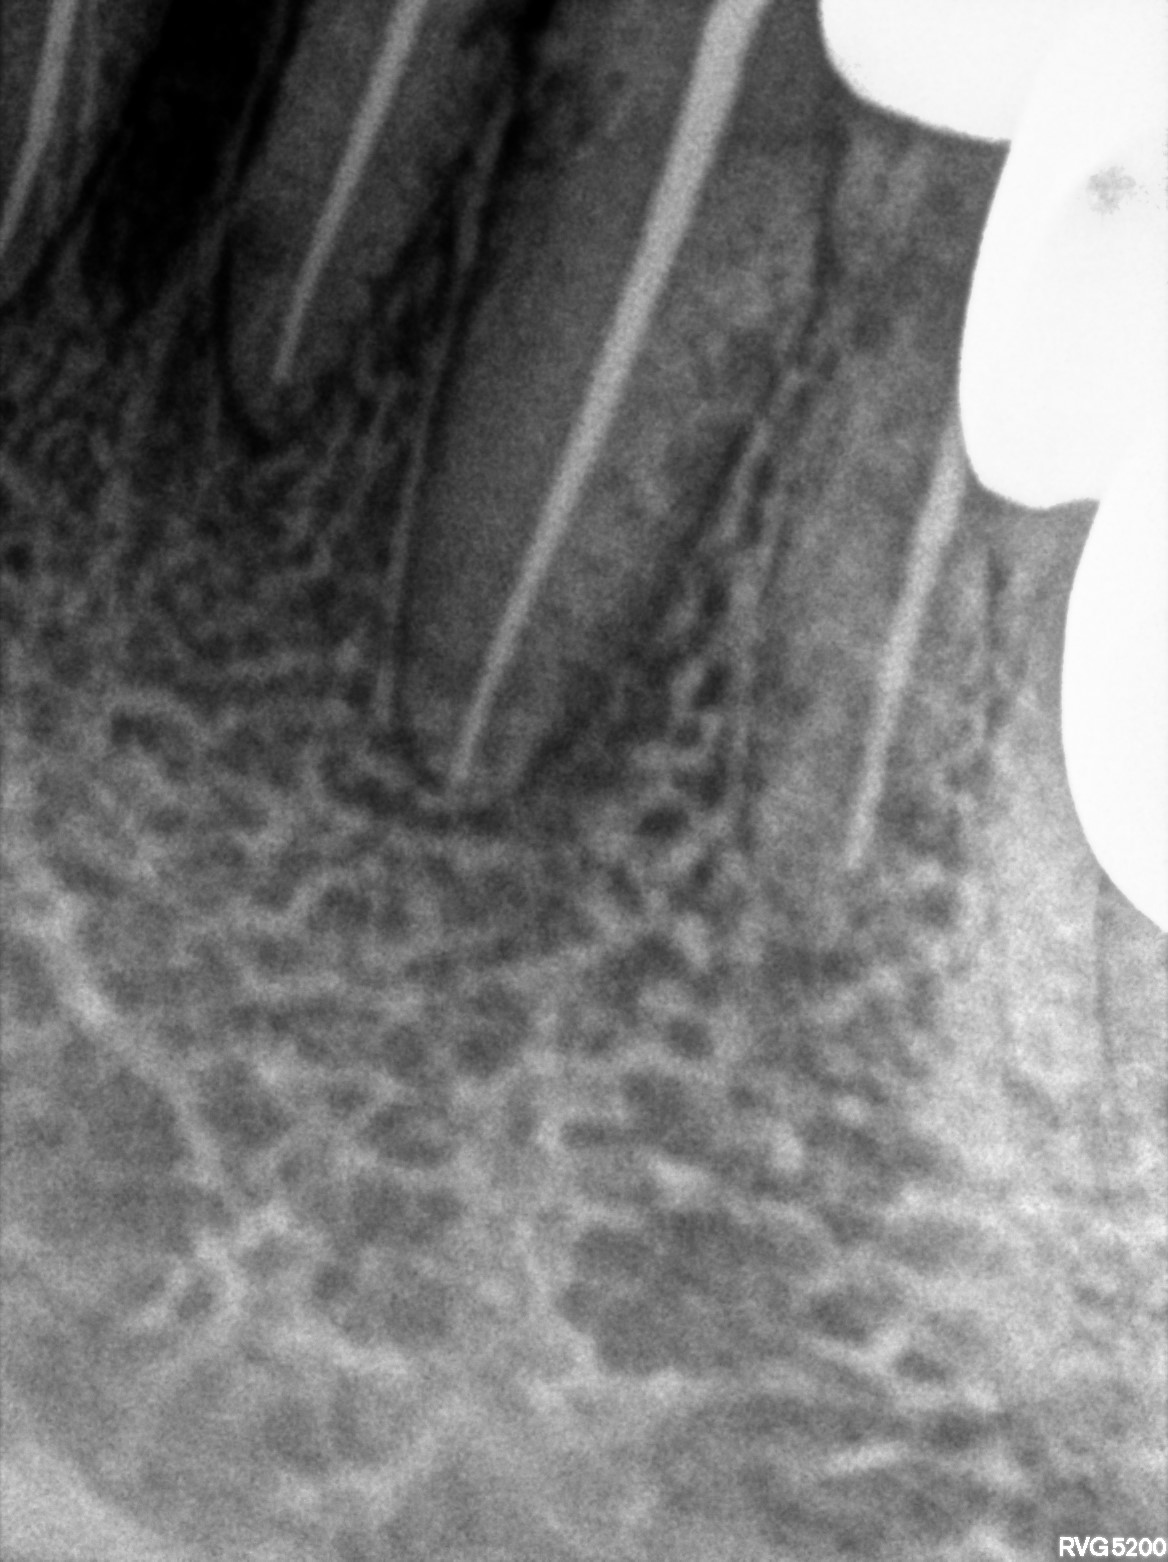

Dental Radiographs FHIR: DocumentReference · LOINC 24641-7

d (1).jpg

24641-7